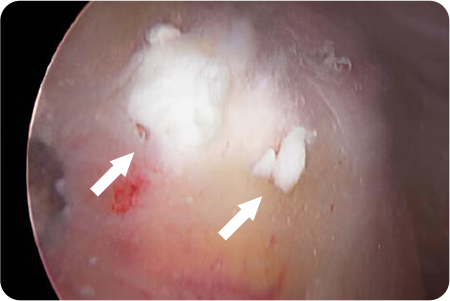

석회제거술

어깨 힘줄 조직에 석회질이 침착하여 발생하게 되는

석회성건염이 있을 때 시행하게 됩니다.

관절경을 이용해 석회주변부에서 염증이 생긴

점액낭을 제거함과 동시에 석회 침착물을 제거

합니다.